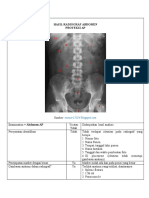

Gambar radiograf Mandibula PA

Examination = Mandibula Ya atau Deskripsi Hasil Analisis

PA Axial Tidak

Gambaran anatomi dalam Ya Tampak gambaran kedua ramus dan

radiogfraf corpus mandibula simetris

Keseluruhan mandibula tidak terpotong

Tampak condylus mandibula

Apakah gambaran anatomi Ya Sesuai, condylus mandibular dan angulus

tampak sesuai dengan mandibular tampak terproyeksi dengan jelas

proyeksi ini?

Apakah kolimasi lapangan Ya Kolimasi sesuai dengan lapangan penyinaran

radiasi cukup dan tetap obyek yang di periksa

mengindahkan prinsip

ALARA?

Proteksi radiasi Tidak Tidak ada alat proteksi radiasi yang

menghalangi gambar objek? menghalangi gambaran hasil radiograf

Garis tepi tulang,patern Ya Tepi luar tulang,trabekula tulang,softtissue

trabekula,dan atau struktur terlihat tajam

soft tissue terlihat tajam

Radiograf terlihat tanpa Ya Tidak terlihat kekaburan gambaran radiograf

distorsi

Ukuran film benar Ya Ukuran film sesuai

Menggunakan alat penerima Ya Ukuran kaset sesuai

gambar yang sesuai

Kecukupan daya penetrasi Ya Sudah menggunakan faktor eksposi dengan

sinar dengan kerapatan? tepat

Kecukupan kontras gambar Ya Sudah dapat menampakkan perbedaan antara

soft tissue dan tulang

Upaya pencegahan terhadap Ya Tidak terlihat artefak yang menggangu

artefak gambaran radiograf

Outcome yang di kehendaki Ya Tampak anatomi yang sesuai proyeksi,region

(contoh : pemakaian sinar-x of interest tepat,dan terlihat jelas dengan

dapat memperlihatkan nilai densitas dan kontras yang cukup sehingga

diagnostik dari regio organ dapat menegakkan diagnosa

anatomi)?

Kesimpulan gambar ini

adalah:

DI TERIMA/ACCEPTED

DI TOLAK/REJECTED Ya Tidak terdapat ID RS, ID Pasien

Jika ditolak/rejected apa Di beri ID RS agar ada pihak yang

upaya yang sebaiknya bertanggung jawab dalam pembuatan

dilakukan dengan cara yang radiograf, diberi ID pasien agar radiograf

berbeda untuk memperbaiki tidak tertukar dengan radiograf pasien lain,dan

ketidaksesusaian teknik di beri marker karena marker merupakan hal

yang telah dilakukan terpenting dalam sebuah radiograf.